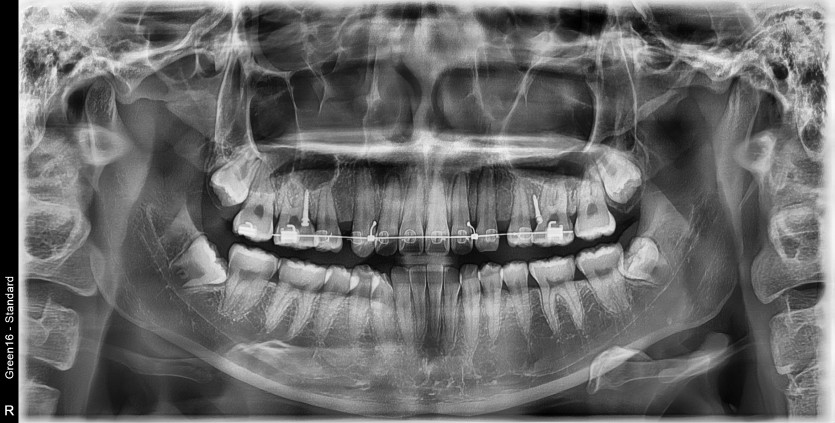

#38,48 사랑니 발치

구강 외과 전문의가 당일 발치했습니다.